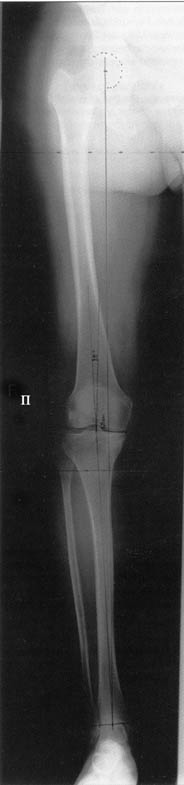

Поводом для проведения всех корригирующих остеотомий у исследуемых пациентов служил гонартроз 1-3 стадии, косметическая коррекция в большинстве случаев являлась вторичной.

Хотя любого больного она не в меньшей степени интересовала. При всех видах остеотомий обязательным требованием являлась восстановление баланса пассивных и динамических сил путем восстановления оси конечности, стабильности связочного аппарата и контроля над мышечной активностью при осевой нагрузке. Как правило, учитывалась сохранность гиалинового хряща на компенсирующем нагрузку мыщелке бедра или большеберцовой кости. Предоперационное планирование осуществляли с поднагрузочных рентгенограмм обоих конечностей.

Дополнительными методами диагностики являлось измерение внутрикостного давления в зоне гипернагрузки и радионуклидные исследования нуклидами технеция. Применялись различные варианты остеотомий на различных сегментах. Для коррекции варусной-торсионной деформации:

высокие плюс, минус остеотомии большеберцовой кости,косая остеотомия малоберцовой. Для коррекции вальгусной деформации применялась плюс, минус надмыщелковая остеотомия бедренной кости. Фиксацию при высокой подмыщелковой остеотомии производили уникальной клинковой пластиной и тяговыми кортикальными винтами. Угол коррекции выставлялся

специальным угломером и направителем.